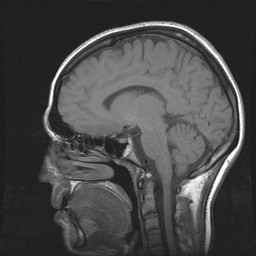

Schedel